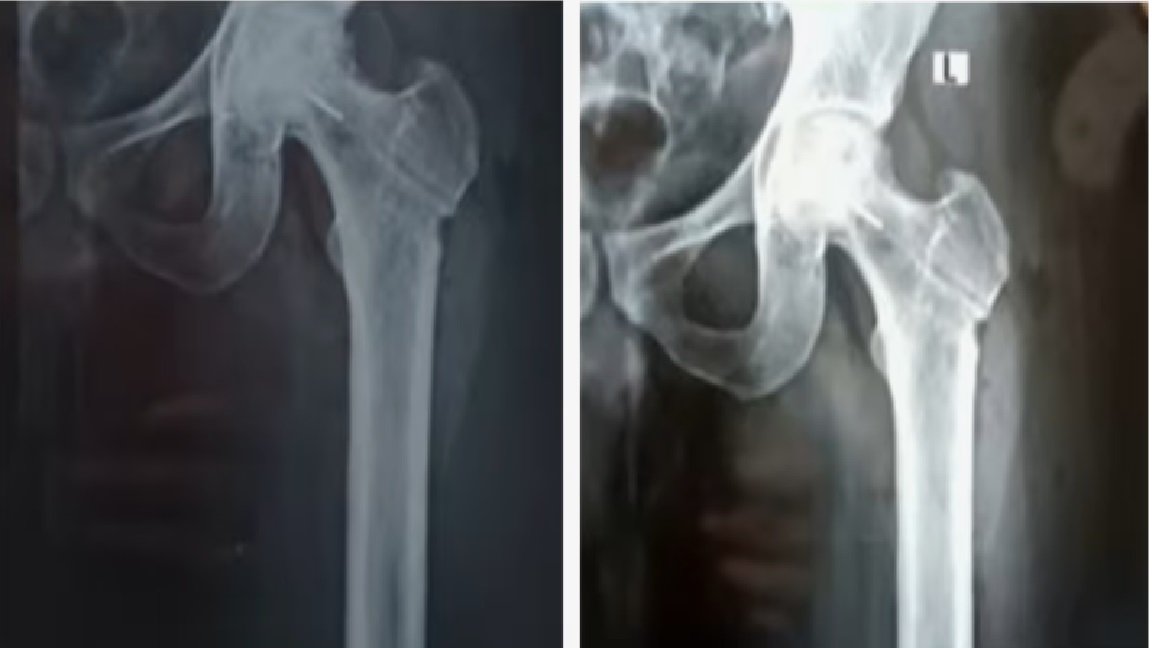

തിരുവനന്തപുരം. തിരുവനന്തപുരം ജൂബിലി മെമ്മോറിയൽ ആശുപത്രിക്കെതിരെ ഗുരുതര ചികിത്സാപിഴവ് പരാതി. ഇടുപ്പ് എല്ലിൽ ശസ്ത്രക്രിയ ചെയ്യുന്നതിനിടെയാണ് ചികിത്സ പിഴവുണ്ടായിരിക്കുന്നത്. രക്തയോട്ടം കൂട്ടാനുള്ള ശസ്ത്രക്രിയക്കിടെ ഡ്രിൽ ബിറ്റ് ഒടിഞ്ഞു കയറുകയായിരുന്നു. മലയിൻകീഴ് സ്വദേശി ജിജിൻ ജോസിൻെറ ഇടത് ഇടുപ്പ് എല്ലിലാണ് ഡ്രിൽ ബിറ്റ് ഒടിഞ്ഞു കയറിയത്. ജിജിൻെറ പരാതിയിൽ കൻോൺമെന്റ് പൊലീസ് കേസെടുത്തിട്ടുണ്ട്. ലോഹ കഷണം നീക്കം ചെയ്യാനാകില്ലെന്നും ലോഹ കഷണം ഇരിക്കുന്നതിനാൽ പ്രശ്നങ്ങളുണ്ടാകില്ലെന്നും രോഗിയെ അറിയിച്ചതാണെന്ന് ആശുപത്രി അധികൃതർ വ്യക്തമാക്കുന്നു.